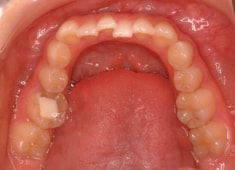

症例紹介

先天欠如歯両側上顎3番

治療法:フルパッシブブラケット:T21

治療後(2年9ヶ月後)